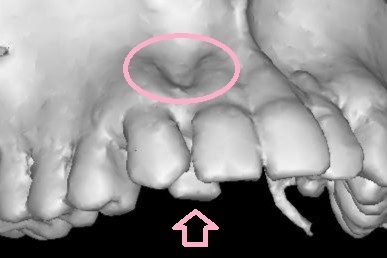

初診時に大きく中に入っていた上の右2番目(向かって左側2番目)の前歯

これを理想と思われる位置にもっていきたかったのですが

初診時のCT(3Dのレントゲン)を細かく分析すると

理想の位置に移動させてしまうと

最悪歯が骨から抜けてしまい抜歯に至る可能性がありました

(専門用語でフェネストレーションといいます)

下にCTの画像を載せておきます

〇部分が骨がないところ 矢印の歯を理想の位置までは動かせません